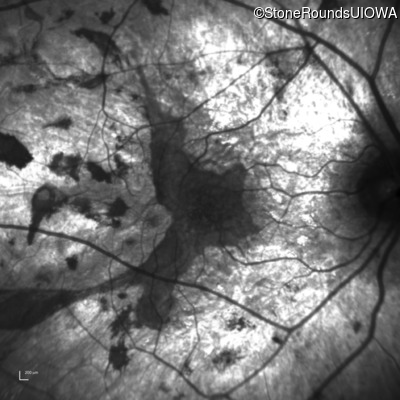

Age at visit: 35 years

This 35-year-old man has trouble in low light and when moving around in busy places. He first reported trouble seeing in low light at age 13. His maternal grandfather was similarly affected.

Age at visit: 37 years